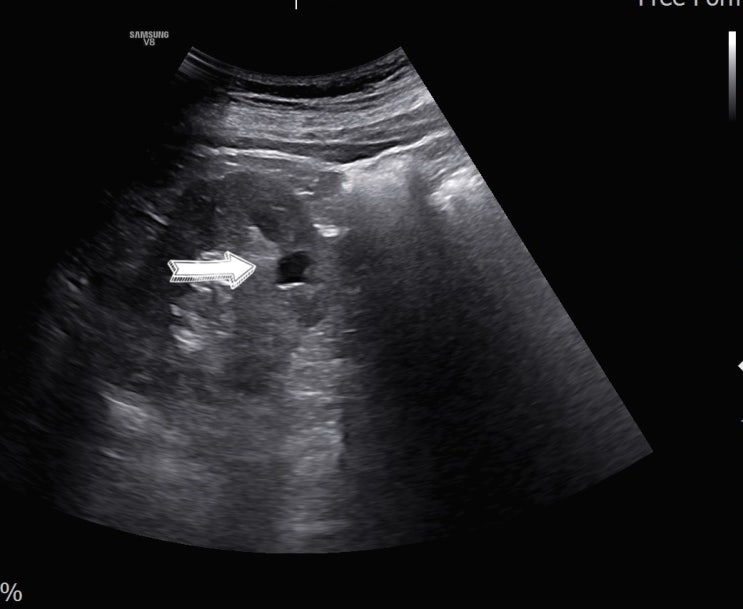

[왕십리 경부초음파] 서울으뜸내과, 목에 만져지는 멍울로 진단된 림프종

#서울으뜸내과 #목초음파 #경부초음파 #림프절비대 #림프종 #왕십리검진내과 #상왕십리검진내과 #행당동검...